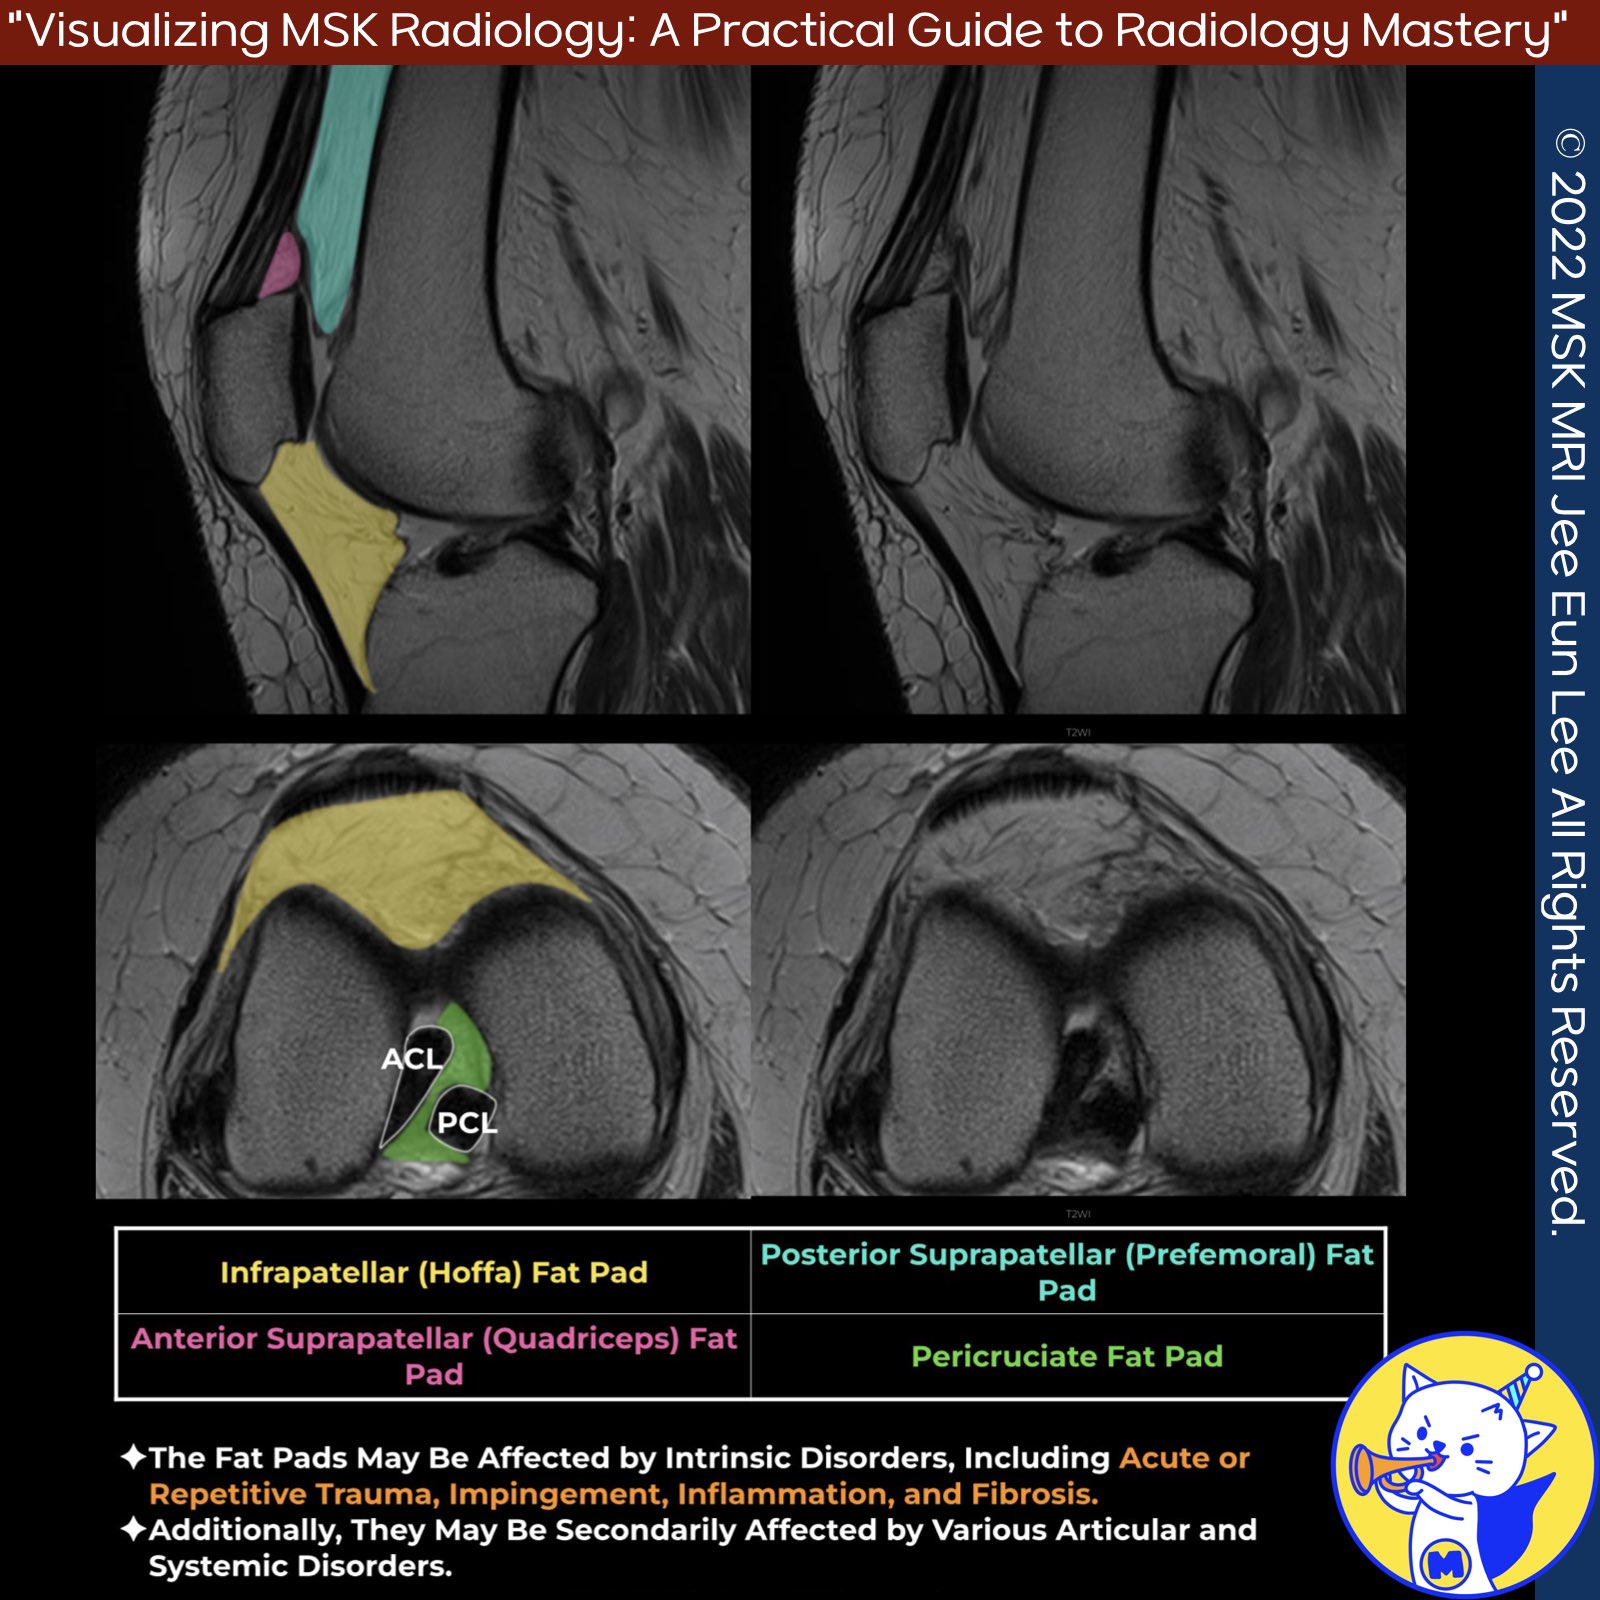

📌 Anatomy of the Fat Pads

- The fat pads of the knee are subject to various intrinsic disorders such as acute or repetitive trauma, impingement, inflammation, and fibrosis.

- These structures may also be secondarily affected by a range of articular and systemic disorders.

1️⃣. Infrapatellar (Hoffa) Fat Pad

- Hoffa's fat pad is located anteriorly by the patellar tendon and joint capsule, superiorly by the inferior pole of the patella, inferiorly by the proximal tibia and the deep infrapatellar bursa, and posteriorly by the joint synovium.

- It is the most sensitive tissue in the knee, richly innervated by branches of the femoral, common peroneal, and saphenous nerves.

2️⃣. Posterior Suprapatellar (Prefemoral) Fat Pad

- The posterior suprapatellar fat pad, also known as the prefemoral fat pad, is situated anterior to the distal femur and superior to the trochlea.

- It is separated from the quadriceps fat pad by the suprapatellar bursa.

3️⃣. Anterior Suprapatellar (Quadriceps) Fat Pad

- The quadriceps fat pad is a small triangular structure located superior to the patella and deep to the quadriceps tendon.

- It is separated from the prefemoral fat pad by the suprapatellar bursa. This fat pad is believed to promote stress dissipation or act as a mechanosensory organ.

4️⃣. Pericruciate Fat Pad

- The pericruciate fat pad fills the gap between the anterior and posterior cruciate ligaments.

- Similar to the anterior fat pads of the knee, it is intracapsular and extrasynovial.

- It appears as a triangular-shaped structure in the sagittal plane, located above the posterior cruciate ligament and posterior to the fibers of the anterior cruciate ligament.